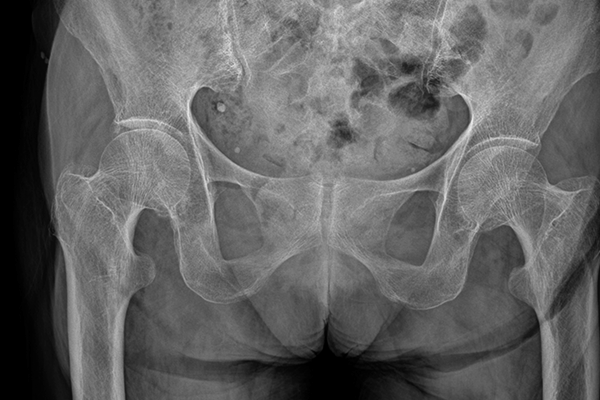

One patient was lost to follow-up. All patients were free of pain, no complications, shoe conflict or misalignement were reported after 12 months of follow-up. No Mg screws were surgically removed. An additional fixation of the distal fibula or the dorsal tibial fragment with conventional titanium implants (Ti) was performed in 17 patients. Within 12 months after primary refixation, 12 of these patients (71%) underwent a second surgery for Ti hardware removal. The mean AOFAS score was 89.8±7.1 and the difference between the treated and the non-treated site in the ROM of the talocrural joint was 2°±11° after 12 months. Radiolucent areas around the screws were attributed to degradation and did not affect clinical or functional outcomes. After one year, the Mg screw heads could not be detected in the plane radiographs of 17 patients which suggests that the majority of the screw head is degraded without introducing adverse reactions.

In this sheep model, after 13 months, the 29-mm screws (initial volume: 198 ± 1 mm 3 ) degraded by 41% (116 ± 6 mm 3 , mean difference 82 [95% CI 71 to 92]; p < 0.001), and after 25 months by 65% (69 ± 7 mm 3 , mean difference 130 [95% CI 117 to 142]; p < 0.001). After 13 months, the 24-mm screws (initial volume: 174 ± 0.2 mm 3 ) degraded by 51% (86 ± 21 mm 3 , mean difference 88 [95% CI 52 to 123]; p = 0.004), and after 25 months by 72% (49 ± 25 mm 3 , mean difference 125 [95% CI 83 to 167]; p = 0.003). After 13 months, the 16-mm screws (initial volume: 112 ± 5 mm 3 ) degraded by 57% (49 ± 8 mm 3 , mean difference 63 [95% CI 50 to 76]; p < 0.001), and after 25 months by 61% (45 ± 10 mm 3 , mean difference 67 [95% CI 52 to 82]; p < 0.001). Histologic evaluation qualitatively showed ongoing resorption with new bone formation closely connected to the resorbing screw without an inflammatory reaction. In patients treated with Mg-alloy screws after a mean of 2.5 years, the implants were radiographically not visible in 17 of 18 patients and the bone had homogenous texture in 15 of 18 patients. No clinical or patient-reported complications were observed.

In this sheep model, Mg-alloy (ZX00) screws showed a resorption to one-third of the original volume after 25 months, without eliciting adverse immunologic reactions, supporting biocompatibility during this period. Mg-alloy (ZX00) implants were not detectable on radiographs after a mean of 2.5 years, suggesting full resorption, but further studies are needed to assess environmental changes regarding bone quality at the implantation site after implant resorption.